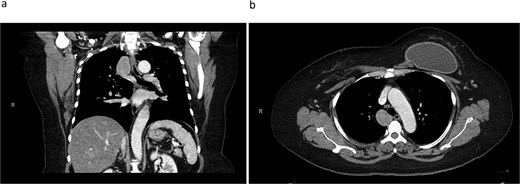

A 45-year-old female with past medical history of hypertension and unspecified connective tissue disorder presented to the emergency room with leg pain, chest pain, and dyspnea with initial blood pressure of 197/138 due to medication noncompliance. Due to the constellation of symptoms combined with severe hypertension, CT chest was ordered to rule out aortic dissection. The scan did not show aortic dissection but incidentally found 4 cm azygos vein aneurysm. The patient had resolution of symptoms, blood pressure was control with medications, and she has been followed outpatient for the azygos vein aneurysm with conservative management of daily aspirin and annual CT thorax scans for 4 years. Four years later, she presented to our clinic with no symptoms of chest pain, dyspnea, cough, and so on but wanted to discuss surgical options. Her most recent CT thorax revealed a stable azygos vein aneurysm measuring 4 cm (Fig. 1). After discussing the risks and benefits of surgery, the patient consented to surgical resection. The patient then underwent robotic assisted mediastinal mass resection with no complications. The intra-operative findings included a hemorrhagic multi-cystic appearing lesion which was connected to the azygos vein as well as the apex of the right lung (Fig. 2). This lesion was isolated with electrocautery and blunt dissection; proximal and distal control of the azygos vein were transected with a surgical stapler and chest tube was placed (Fig. 3). Postoperatively, patient recovered well, chest tube was removed, and she was discharged home on postoperative day one. Surgical pathology was benign and revealed a portion of lung parenchyma with associated dilated blood vessels. She is doing well and has no cardiac or pulmonary symptoms 2 years after surgery.

CT thorax revealing a 4.1 × 3.3 cm azygos vein aneurysm. a) Coronal view. b) Transverse view.